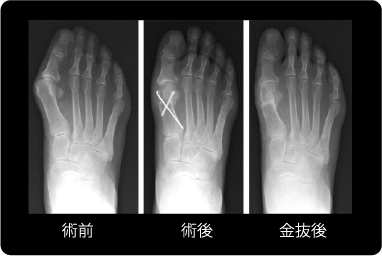

Mann変法

変形が比較的強い例に対して選択している手術方法です。

母趾の付け根の骨(第一中足骨)を遠位内側の出っ張りを削り、近位でドーム状に骨切りして矯正後に特殊なネジ2本で固定し、母趾内転筋(鼻緒をつまむ力の筋)を母趾の基節骨から切り離して、中足骨の頸部に開けたトンネルに通して固定します。

Mann変法の説明図